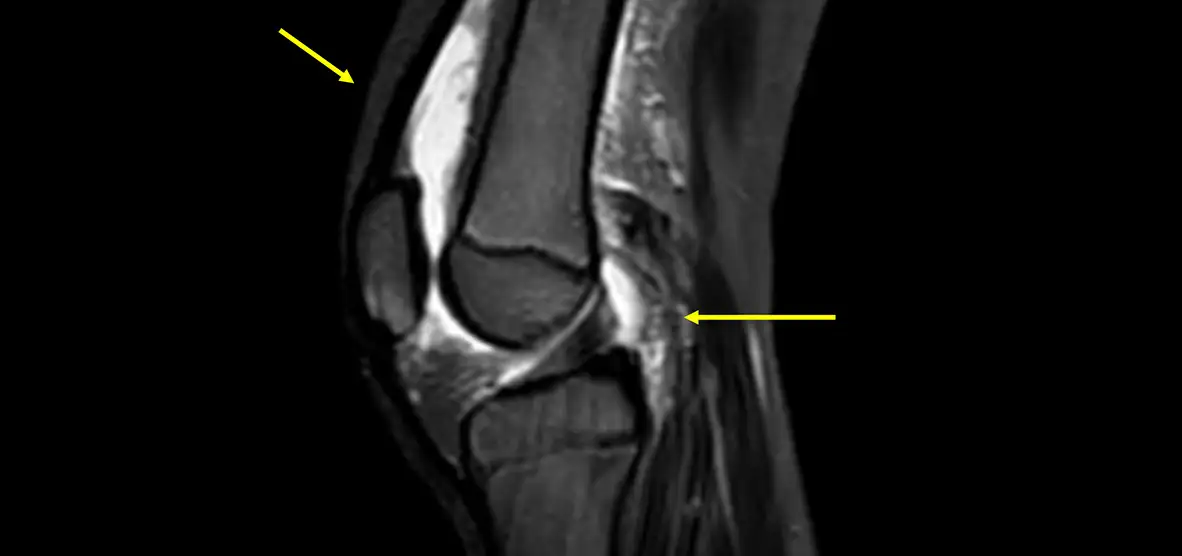

Musculoskeletal infections may involve the bone (osteomyelitis), the soft tissues (cellulitis, myositis), or a joint (septic arthritis). These infections may be caused by a bacterial infection in the blood stream or an open wound, a severe fracture of the bone, or complications from surgeries. Musculoskeletal infection may be suspected if your child has had a recent injury or surgery, pain with redness and swelling in the area, a fever, and/or elevated inflammatory markers shown in bloodwork.

It is important to diagnosis and treat musculoskeletal infections quickly to prevent worsening symptoms or to prevent the infection from spreading to other areas of the body. These infections can be treated with antibiotics but may require surgery to drain an abscesses or joint effusions.

Dr. Meyers, chief of Musculoskeletal Radiology, worked with system engineers and our own MRI physicist, Jean Tkach, to develop a Rapid MRI for Acute Musculoskeletal Infection protocol that can accelerate a diagnosis, treatment, and recovery. MRIs are notorious for being long exams, but with this specific protocol, the entire exam can be completed in less than ten minutes. Because the exam time is so short, this exam can easily be added to our busy MRI schedule and can be performed without sedation or anesthesia. It is important to understand that this particular exam needs to be approved by attending physicians and only used when your child’s symptoms and history match our protocol guidelines.